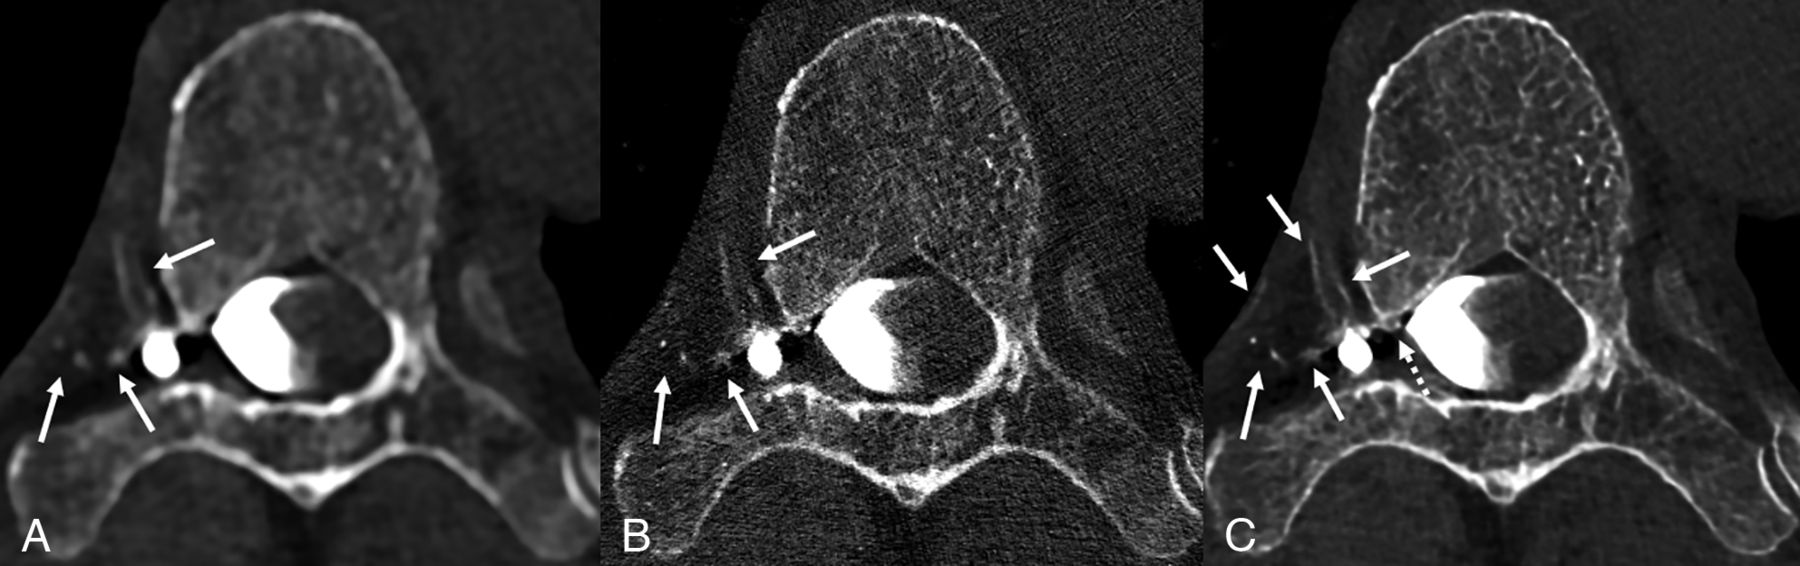

Axial low-energy thresholded (T3D) images in a 70-year-old man with a right T6 CVF. Images were reconstructed using a Br56 kernel (A), a sharper Qr89 kernel (B), and a Qr89 kernel after denoising with the trained model (C), all presented at the same section and window/level settings. Hazy opacification of the external vertebral venous plexus is evident using the smoother Br56 kernel (A, arrows). These external vertebral veins are poorly visualized using the Qr89 kernel secondary to noise (B, arrows). The denoised Qr89 image most clearly delineates all the involved veins, including multiple veins of the external vertebral venous plexus (C, solid arrows), and definite involvement of the internal vertebral venous plexus (C, dashed arrow).